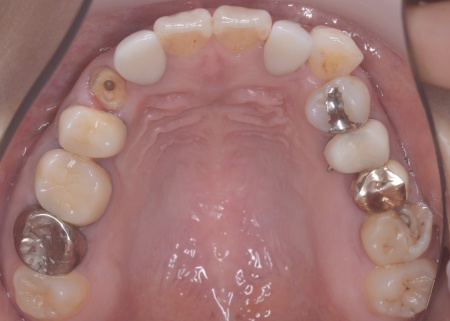

| カウンセリング | 拝見したところ、左下と右上の歯はともに大きな虫歯があり、歯だけでなく被せ物を支える土台の部分にも影響が及んでいました。

さらに、ほかの歯に入っている詰め物や被せ物の周囲にも、過去に治療した部分に再び虫歯ができる二次カリエスが複数見つかりました。 また、噛み合わせを確認したところ、奥歯で噛み合わせた際に上下の前歯が当たらず隙間ができる開咬(かいこう)が認められました。 実際に患者様の場合も、特定の歯に長期間強い力がかかり続けたことで歯や修復物の破損、さらには口腔内全体のトラブルにつながった可能性が高いと考えられました。 修復治療が必要でしたがこの噛み合わせの問題を改善しないまま行うと、治療した歯に再び過度な力が加わって被せ物の破損・脱離や虫歯の再発を招くリスクが高まります。 |